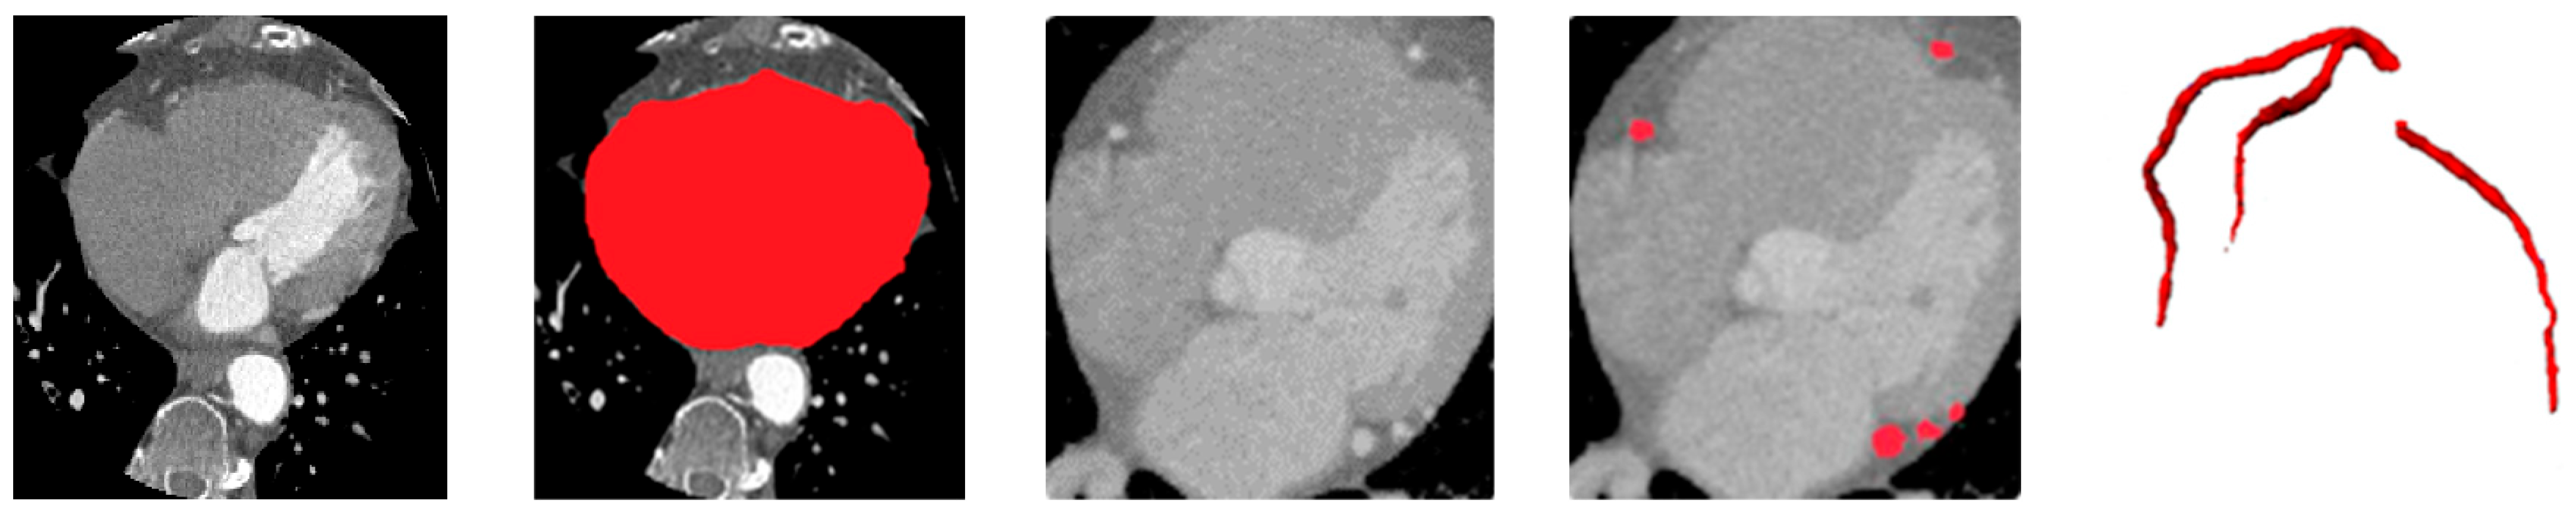

Figure 8. Ablation study showing the contribution of each framework component. From left to right: Residual U-Net (baseline), soft-voting ensemble, rank-based selective ensemble, and rank-based ensemble with vessel priors.

To quantify the contribution of each component within the proposed framework, an ablation study was conducted as summarized in Table 4. Using only the best single model (Residual U-Net) serves as the baseline configuration, representing the strongest standalone learner in our architecture set. Introducing a simple soft-voting ensemble of all U-Net variants yields modest gains, reflecting the benefit of aggregating heterogeneous feature representations but still limited by uniform weighting.

Replacing soft-voting with the proposed rank-based selective fusion provides a more pronounced improvement, as the ranking mechanism prioritizes morphologically consistent, vessel-aligned predictions while suppressing isolated or anatomically implausible responses. The addition of vessel priors to this selective ensemble further refines localization by spatially constraining calcifications to the coronary tree, leading to the highest Dice and sensitivity scores overall.

As observed, the rank-based ensemble improves Dice by approximately +0.95% over soft-voting, while incorporating vessel priors adds a further +1.25% Dice and +1.4% sensitivity gain. These progressive improvements demonstrate that anatomical guidance complements ensemble diversity, yielding the most anatomically coherent and clinically reliable CAC segmentation results.

Figure 8 presents qualitative examples illustrating the progressive improvement across different configurations. The final model with vessel priors produces cleaner, vessel-aligned lesion maps and sharper calcification boundaries compared to the baseline and soft-voting ensembles. The addition of selective fusion and vessel priors progressively improves lesion sharpness, vessel conformity, and reduces false positives around extracardiac regions.